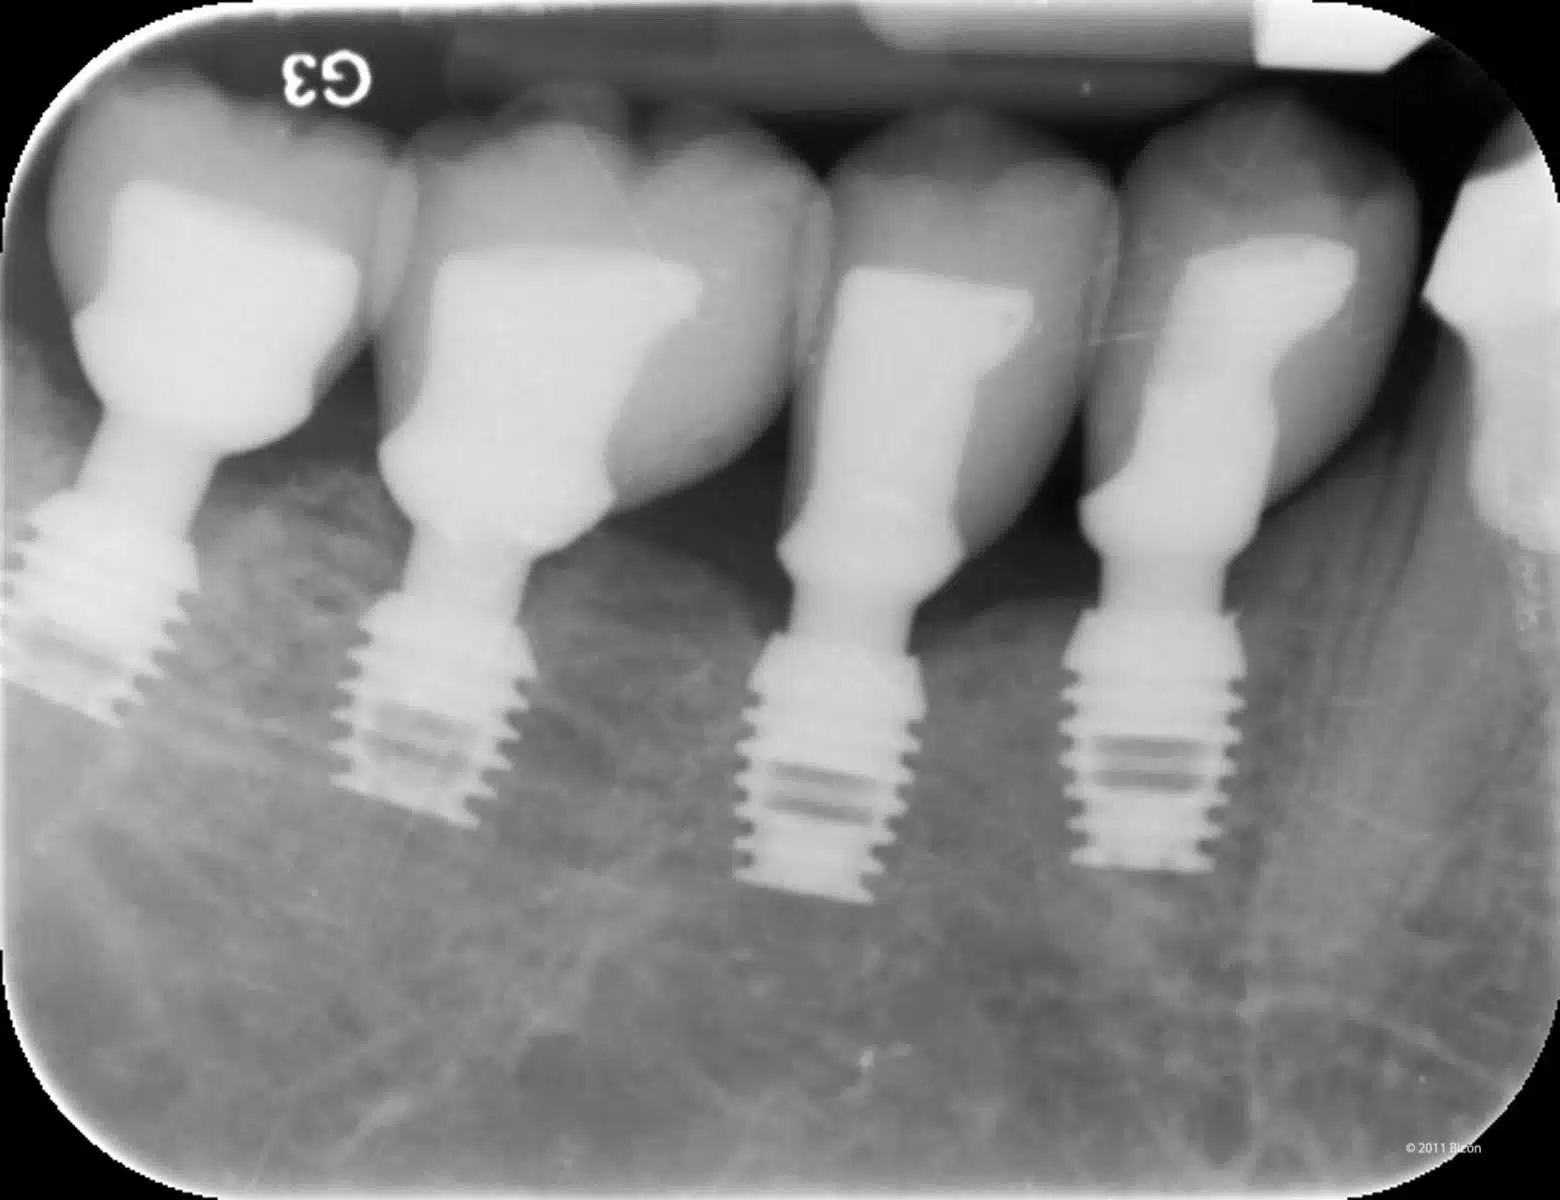

Gli impianti Bicon combinano un design robusto (plateau + Morse taper) con un posizionamento subcrestale strategico. Questa sinergia: Preserva osso e tessuto molle Riduce le complicanze biologiche Offre soluzioni meno invasive anche con osso limitato Con 40 anni di follow-up, la nostra tecnica e il sistema Bicon rappresentano il gold standard per la gestione di casi complessi come questi. Se siamo i numeri uno, un motivo c’è: innovazione, sicurezza e risultati comprovati. Bicon Short: Pionieri di una Rivoluzione.

Vantaggi della soluzione Bicon SHORT®

✅ Recupero dell’osso autologo, favorendo la stabilità a lungo termine dell’impianto.

✅ Connessione conometrica senza vite tra moncone e impianto, riducendo il rischio di micromovimenti e complicanze meccaniche.

✅ Minima invasività con impianti Bicon SHORT e massima efficienza nella gestione protesica.